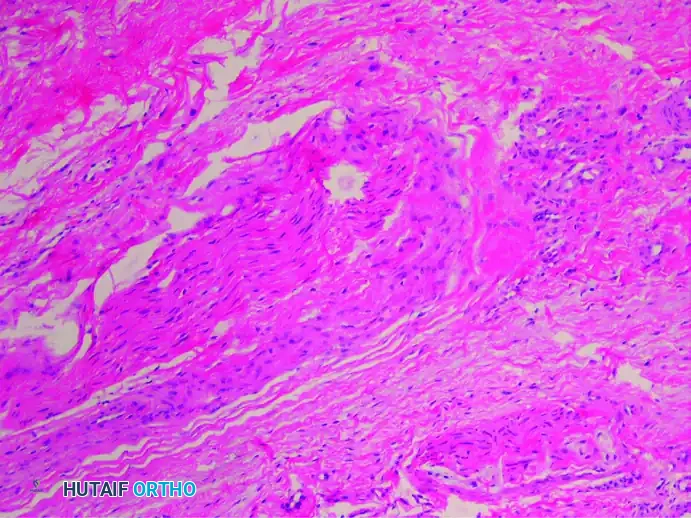

2. Vascular Degeneration (Vasa Nervorum)

There is a markedly increased number of intrafascicular arterioles. However, these vessels are not healthy; they exhibit thickened, hyalinized walls caused by the deposition of multiple layers of basement membranes. Degenerative changes such as the fraying and duplication of the internal elastic lamina are frequently observed, leading to localized nerve ischemia.

(Verhoeff-van Gieson stain highlighting vascular degenerative changes)